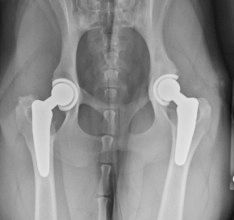

Total Hip Replacement (THR)

THR involves replacing both the femoral head and acetabulum with prosthetic implants, similar to the procedure performed in humans. It provides the best long-term outcome by restoring normal hip function and eliminating pain.

Dogs must be fully grown (>12 months for large breeds or 18 months for giant breeds) to prevent implant shifting with growth. We typically recommend referral to NC State Veterinary Hospital, which performs a high volume of these surgeries each year.